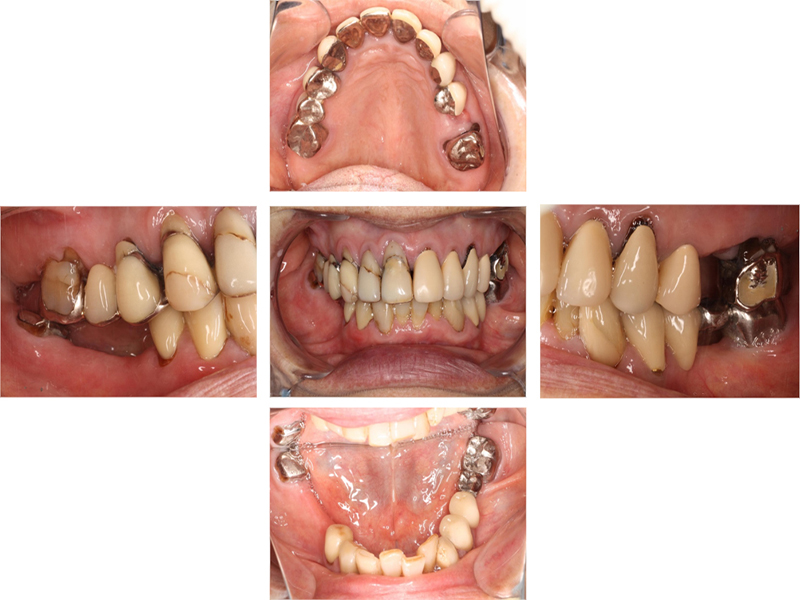

初診時口腔内写真

初診時X線写真